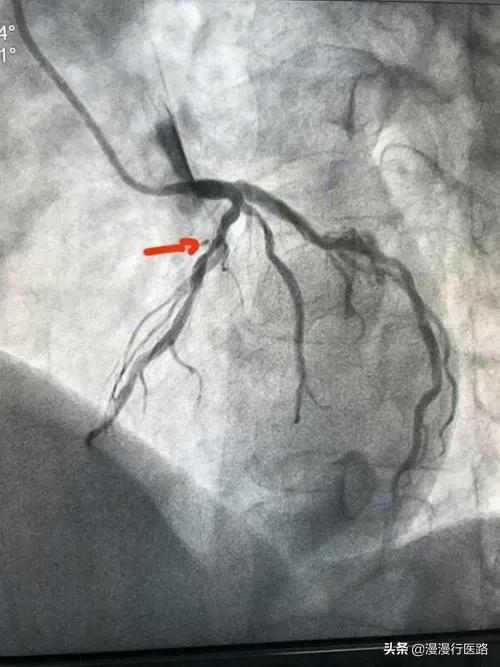

Après plusieurs tentatives de persuasion, Lao Fu a été hospitalisé et j'ai fait en sorte que Lao Fu passe un cardiogramme, qui a révélé qu'un vaisseau sanguin du côté gauche était rétréci à 99 % et immédiatement bloqué, grâce à une détection opportune. Cependant, un stent domestique coûte 7 500 euros, et les autres instruments chirurgicaux des dizaines de milliers d'euros. Pour une famille comme celle de Lao Fu, c'est un véritable fardeau. Il se trouve que le Dr Wang était responsable d'une expérience, à savoir une étude clinique sur le processus de pose de stent, et il a demandé à Lao Fu s'il était prêt à participer à l'étude, afin qu'un stent lui soit posé gratuitement. Lao Fu a accepté avec plaisir, car après tout, cela lui permettrait d'économiser près de 10 000 yuans. Lorsqu'il a renvoyé Lao Fu au service, celui-ci avait toujours l'air inquiet et lui a demandé ce qui n'allait pas.

J'ai alors fait procéder aux examens nécessaires et l'imagerie a montré que la sténose de l'artère coronaire gauche atteignait 85 %, ce qui nécessitait la pose d'un stent.